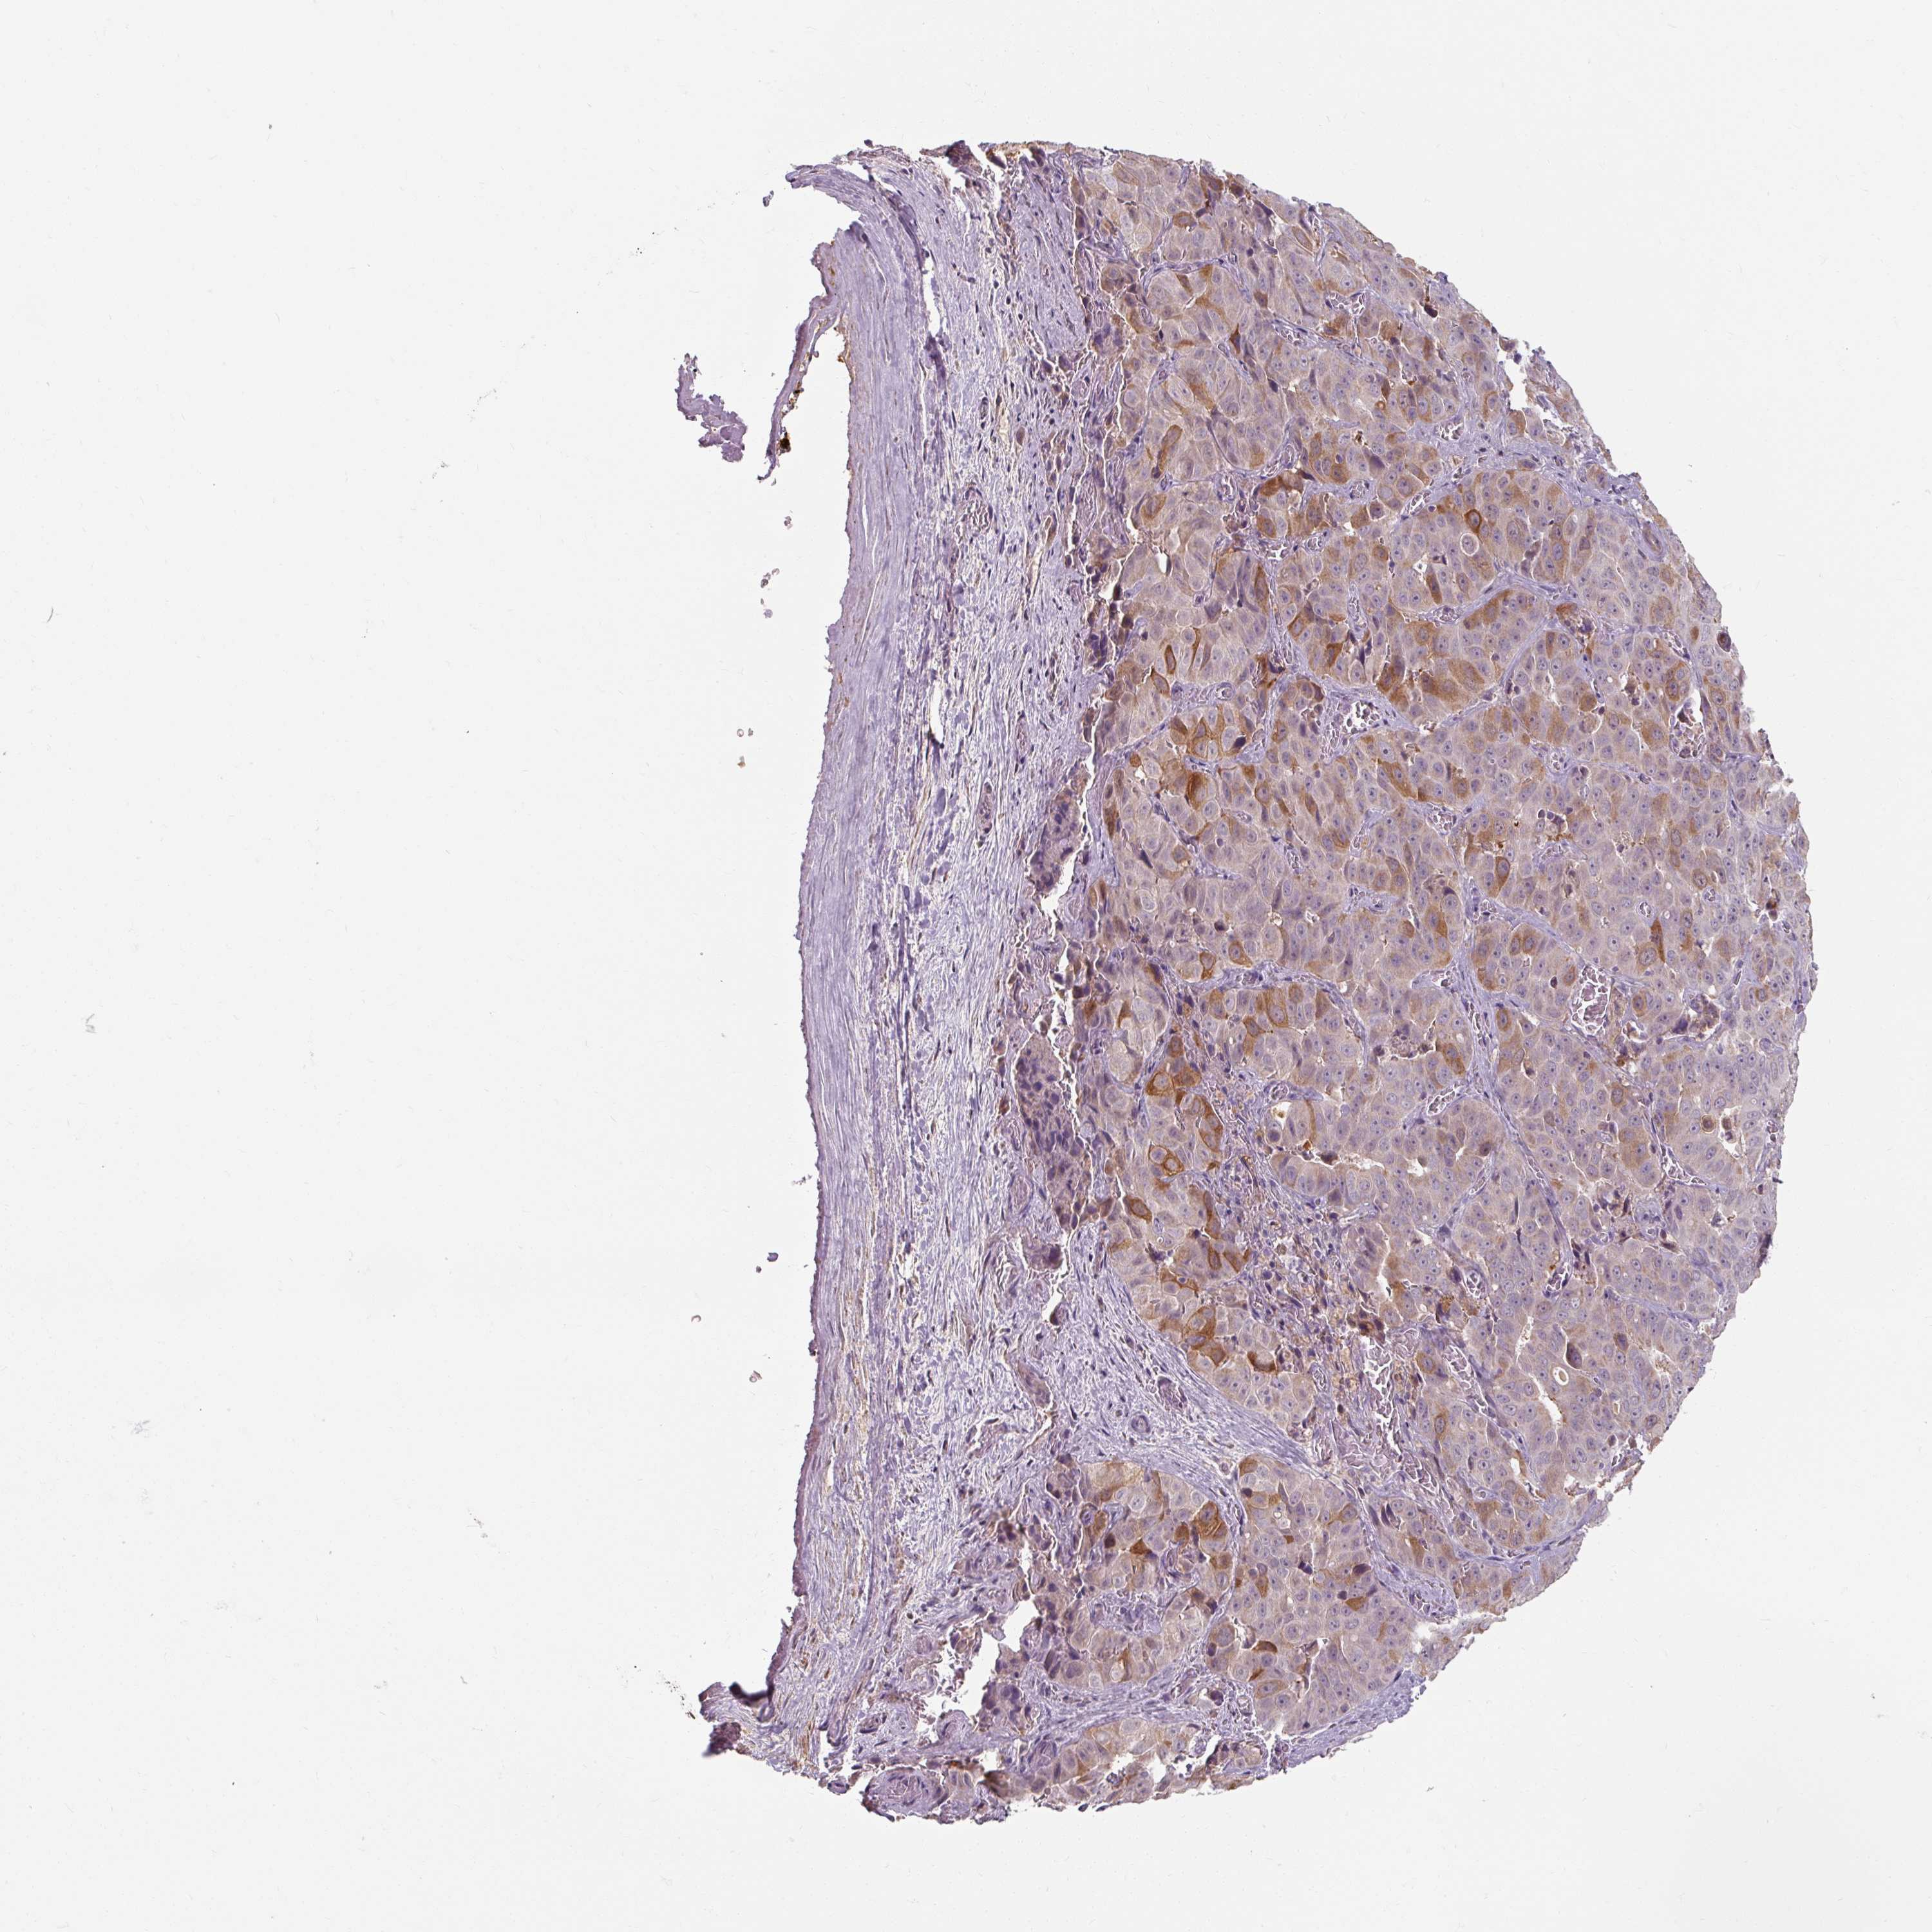

LIVER CANCER - Protein expressioni

A mouse-over function shows sample information and annotation data. Click on an image to view it in a full screen mode. Samples can be filtered based on level of antibody staining by selecting one or several of the following categories: high, medium, low and not detected. The assay and annotation is described here.

Note that samples used for immunohistochemistry by the Human Protein Atlas do not correspond to samples in the TCGA dataset.

Antibody stainingi

Antibody staining in the annotated cell types in the current human tissue is reported as not detected, low, medium, or high, based on conventional immunohistochemistry profiling in selected tissues. This score is based on the combination of the staining intensity and fraction of stained cells.

Each image is clickable and will lead to virtual microscopy that enables deeper exploration of all samples and also displays staining intensity scores, fraction scores and subcellular localization as well as patient and tissue information for each sample.

Antibody HPA053097

Staining

High

Medium

Low

Not detected

Intensity

Strong

Moderate

Weak

Negative

Quantity

>75%

75%-25%

<25%

None

Location

Nuclear

Cytoplasmic/membranous

Cytoplasmic/membranous,nuclear

Cholangiocarcinoma

Carcinoma, Hepatocellular, NOS